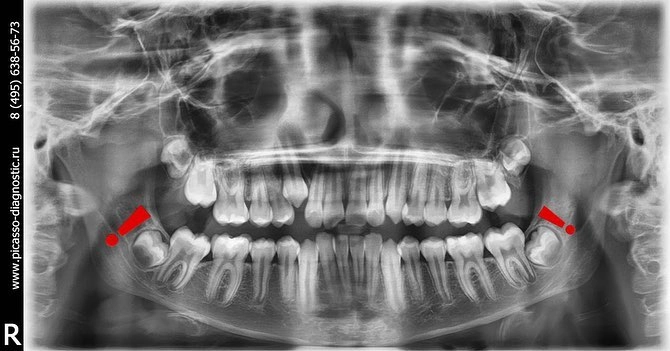

Для ранней диагностики достаточно уже в возрасте 10-12 лет посетить своего стоматолога и сделать ортопантомограмму (снимок всех зубов).

Несколько картинок для понимания и закрепления материала.

Случается, что зачатки зубов мудрости находятся глубоко в челюсти и упираются в корни соседних зубов.

Такие зубы называются ретинированными.

Если же зуб прорезывается не в зубном ряду, а куда-то в сторону, такой зуб называется дистопированным.